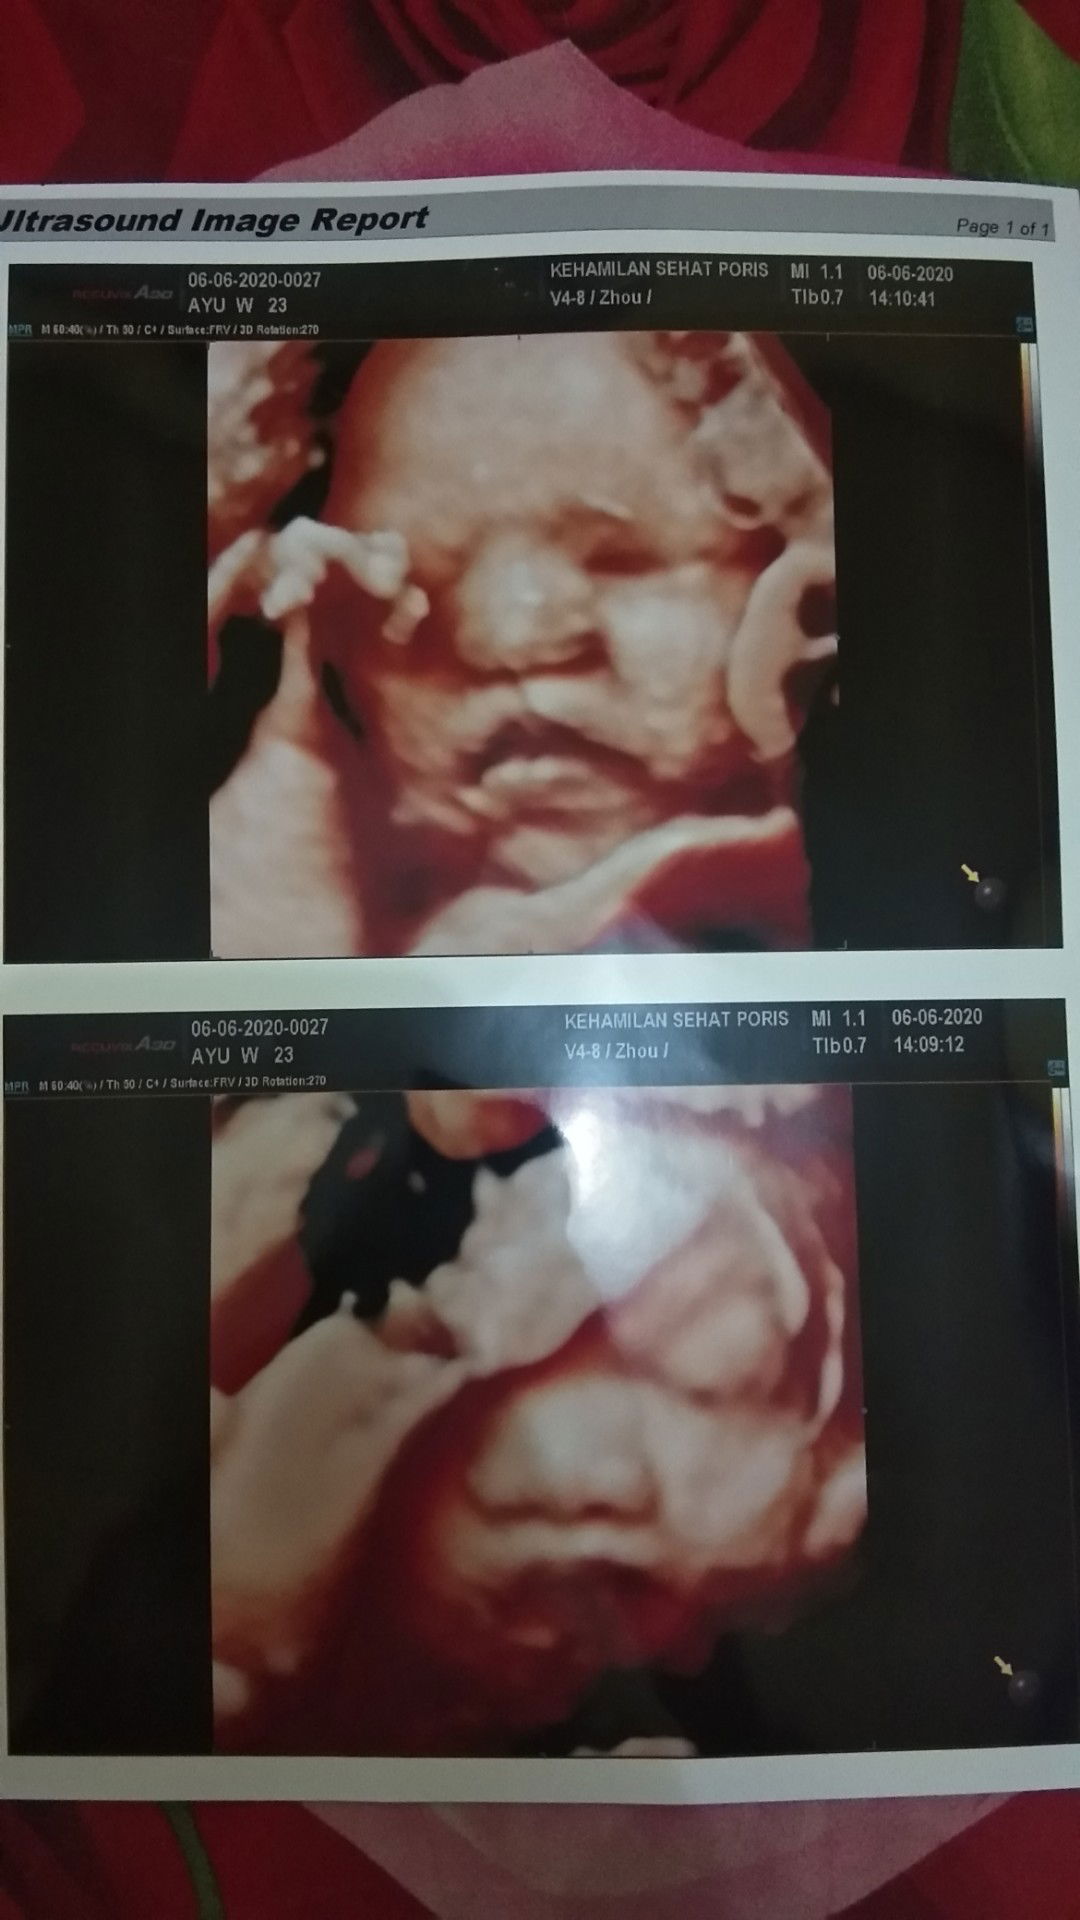

Usg 4d usia kandungan sudah 32week, ternyata baby berjenis kelamin perempuan? padahal selama ini disangkanya baby laki² soalnya aktif bgt dlm perut, hehe sehat² ya sayangnya mamah??